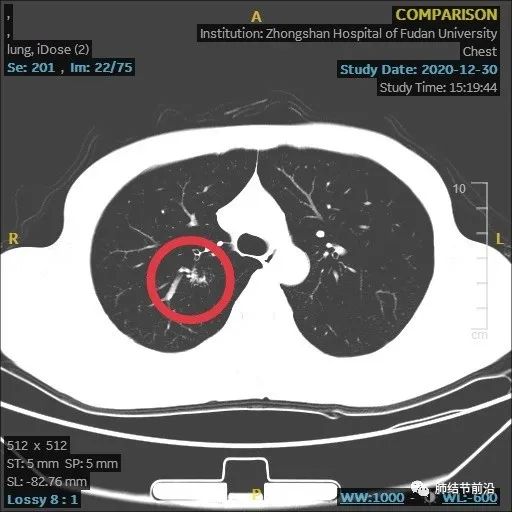

6月后复查,结节发生变化(个人认为,8mm实性结节,首次建议3个月复查)。

结节变大,形态变化,出现多中心微小结节堆积形态,而之前实性8mm结节却不见了。